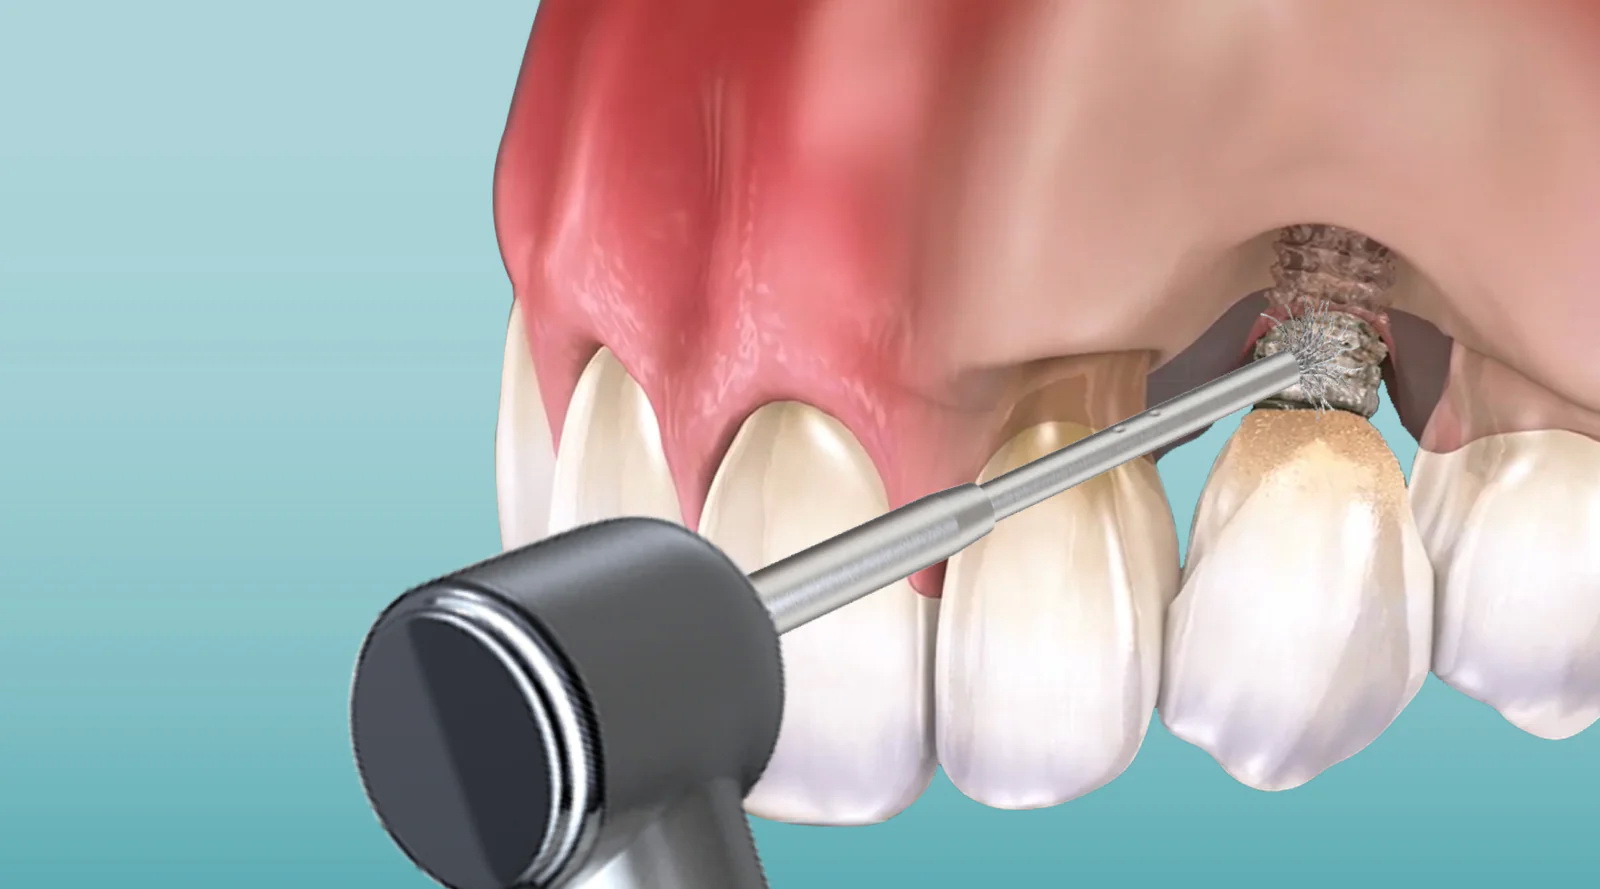

Periodontal Instrumentation & Nonsurgical Therapy

Nonsurgical therapy is the first line of defense against periodontal disease.

You will gain exposure to:

- Hand scaling instruments and their design

- Ultrasonic scaling principles

- Scaling and root planing workflows

- Assisting during periodontal debridement

- Periodontal maintenance protocols

Understanding instrumentation enhances clinical efficiency and improves patient outcomes.

Lasers in Periodontics

Laser therapy is reshaping periodontal treatment.

You will explore:

- Principles of laser-tissue interaction

- Indications for periodontal laser procedures

- Safety considerations

- Workflow integration

Understanding modern periodontal technologies increases your relevance in forward-thinking practices.